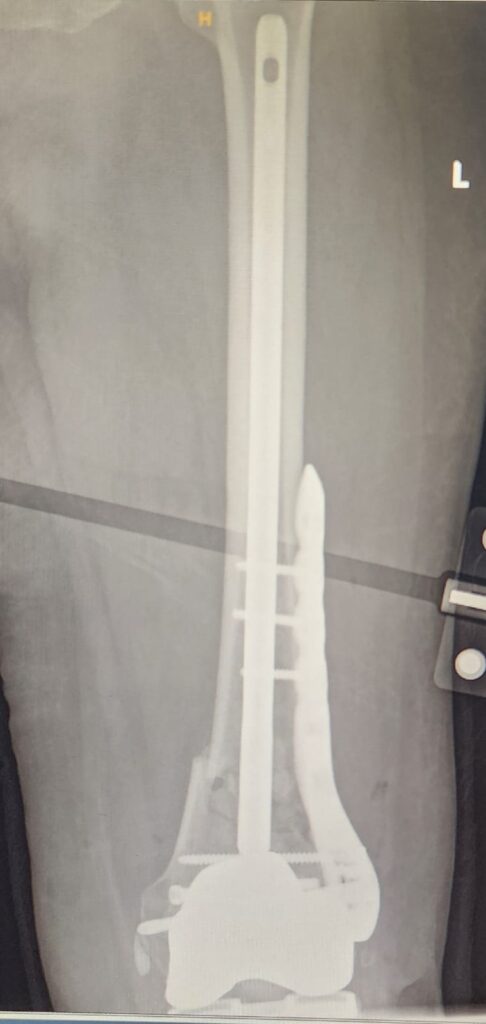

πŸ“Έ X-ray Before Surgery

(Image 1 & 2) – The preoperative radiographs show a clear fracture line around the previously implanted knee prosthesis.

The main concern was maintaining implant stability while achieving fracture union and early mobility.